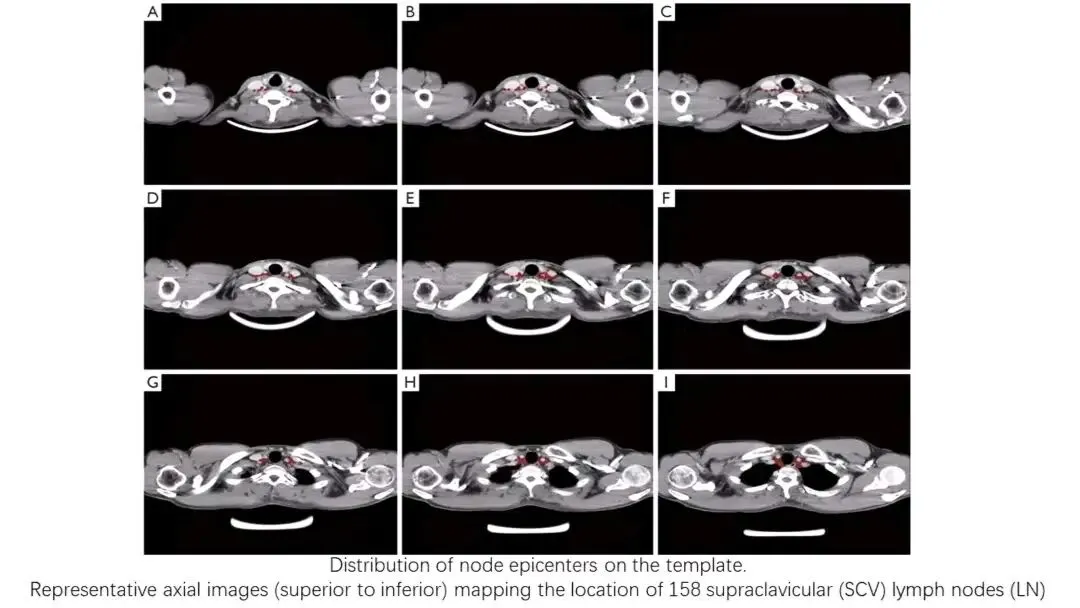

2. 淋巴结评估的重要性:

淋巴结转移极其常见,初诊时总体颈部淋巴结阳性率

转移规律:

上、中颈淋巴结转移率高;

若肿瘤侵犯下咽,则咽后淋巴结转移风险显著增加(下咽后壁癌可达43.5%)。

结论:对于下咽受侵、晚期或淋巴结分期高的患者,需将咽后淋巴结纳入治疗靶区或清扫范围。